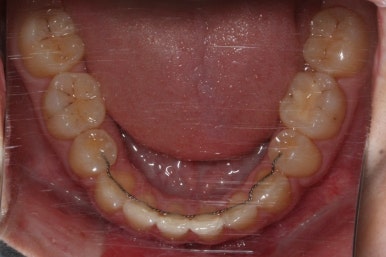

교정치료를 시작한지 3개월 밖에 지나지 않았을 시점인데도 벌써 덧니가 많이 가지런해졌습니다. 치아는 자리만 확보되면 쉽게 가지런해질 수 있습니다.

가지런해지지 않았던 아래 앞니 하나도 금새 가지런해졌습니다.